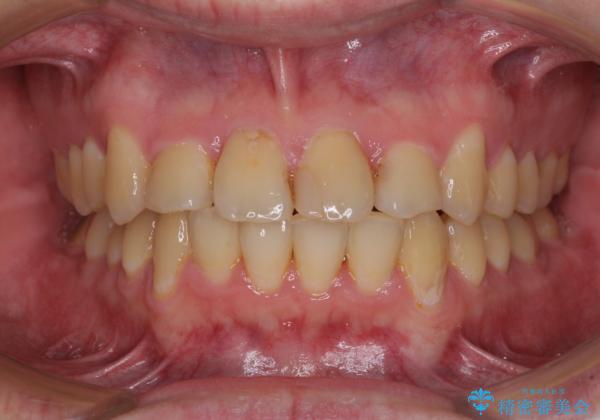

歯列全体のクロスバイトを治したい ワイヤー装置による矯正治療

- 上下のデコボコと前歯のクロスバイトを改善したいとのことで来院された患者様です。

マウスピース矯正での自己管理には自信がないとのことで、ワイヤー装置による矯正治療を行うこととしました。

デコボコの程度は強かったのですが、口元の突出感はなかったため、非抜歯矯正としました。

クロスバイトは、治療の過程で咬み合わせが大きく変化する期間があり、食事が取りにくくなってしまいます。

また、装置が対合歯と咬み合ってしまい、頻繁に脱落するなど、色々と面倒なことがあり、治療がスムーズに進まないことがあります。